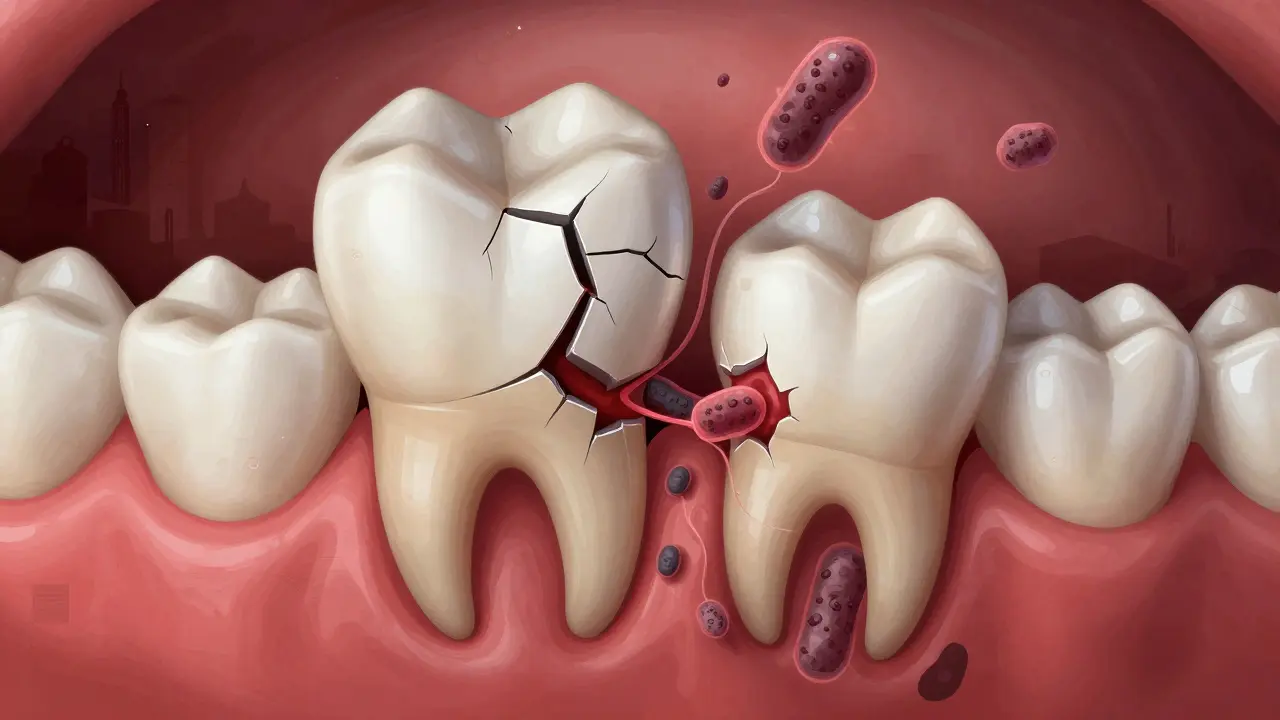

• Trhliny v zubu nebo korunce - I když metalokeramická korunka je pevná, pod ní může být zub poškozený. Například po silné zubní léčbě nebo po úrazu. Malá trhlina se může rozšířit s časem a umožnit vstup bakterií.

• Zánět v okolí kořene (periodontitida) - Někdy bolest pochází ne z vnitřku zubu, ale z okolních tkání. Pokud je zub špatně vyčištěný nebo máte problémy s dásněmi, může se rozvinout zánět v okolí kořene, který se projevuje bolestí i otokem.

Co se děje pod korunkou, když začne bolět?

Pod metalokeramickou korunkou je zub, který už nemá žádný nerv - nebo alespoň neměl mít. Pokud jste měli kanálovou léčbu, nerv byl odstraněn. Ale i bez nervu může zub reagovat na infekci. Zubní kořen je obklopen kostí, která je plná nervů. Když se pod korunkou začne šířit infekce, tato kost se zánětem reaguje - a to způsobuje bolest.

Poškozený zub pod korunkou s bakteriemi šířícími se do kosti